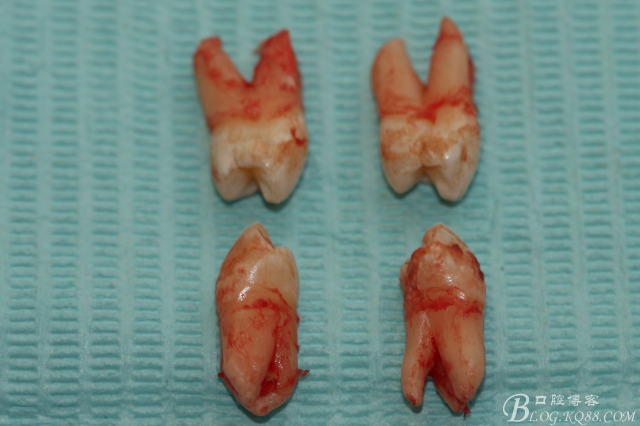

7.四顆離體上下頜第一前磨牙牙根形態(tài)

患者:江某某、男、14歲。因正畸治療需要拔除上下頜四顆第一前磨牙。按醫(yī)囑,局麻下拔除四顆第一前磨牙。牙齒拔除后發(fā)現(xiàn)四顆牙齒均為三個根,頰側(cè)兩根,腭側(cè)一個根。上頜第一前磨牙偶見三根。下頜第一前磨牙左右兩側(cè)均為三根,實屬罕見。發(fā)圖片,與同仁共勉。